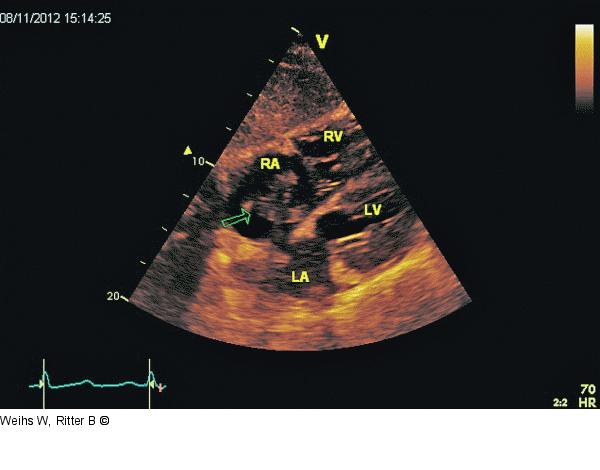

Abbildung 5: Vierkammerblick Subkostaler Vierkammerblick. Flottierender Thrombus (Pfeil) im RA mit Prolabieren in den RV. Dilatierter und hypokontraktiler RV. RV: rechter Ventrikel; LV: linker Ventrikel; RA: rechter Vorhof, LA: linker Vorhof. |

Subkostaler Vierkammerblick. Flottierender Thrombus (Pfeil) im RA mit Prolabieren in den RV. Dilatierter und hypokontraktiler RV. RV: rechter Ventrikel; LV: linker Ventrikel; RA: rechter Vorhof, LA: linker Vorhof. |